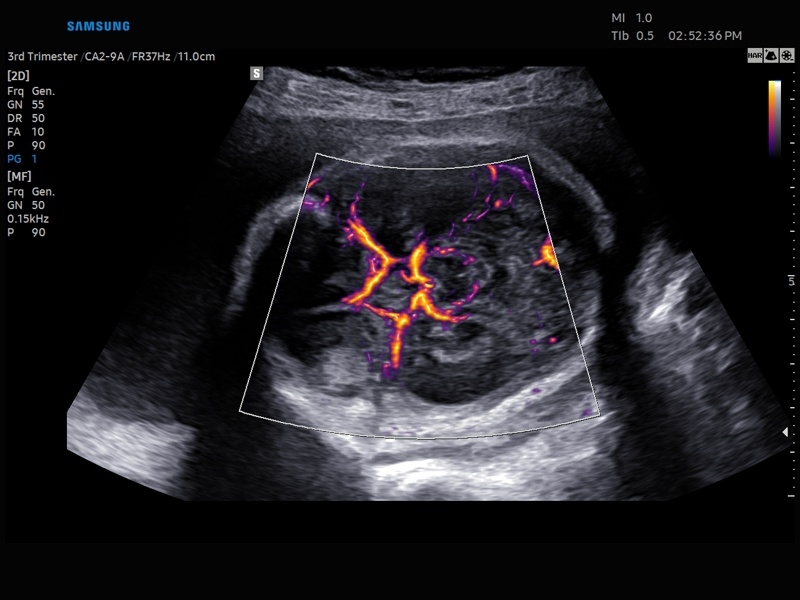

• Акушерство и гинекология

• Технологии визуализации: MV Flow, LumiFlow, SEE Stream, Panoramic

Недопплеровская визуализация кровотока:

Да

• Модуль5D HeartColor – программа автоматического построения основных срезов средца плода в режиме объемного сканирования с анализом кровотока.

• Модуль MV-Flow – программа (режим), позволяющая визуализировать кровоток в микроциркуляторном русле с высоким разрешением без использования контраста.

• Модуль LumiFlow – программа отображения кровотока с объемной графикой для лучшего понимания архитектоники сосудистого русла.

• Программа SEE Stream – режим недопплеровской визуализации кровотока в реальном масштабе времени.

• Модуль MV-Flow - программа (режим), позволяющая визуализировать кровоток в микроциркуляторном русле с высоким разрешением без использования контраста.